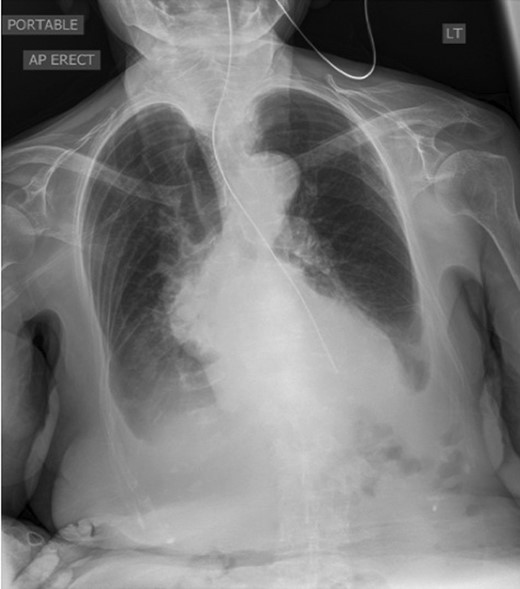

The patient was referred to ENT for endoscopic insertion of a nasogastric (NG) tube as the initial attempt failed. Resistance was noted at 40 cm and failure to pass beyond the lower oesophagus. Chest X-ray revealed the NG tube tip in the distal oesophagus (Fig. 2).

Chest X-ray showing the NG tube blocked at the distal oesophagus. The typical retrocardiac gas filled viscus cannot be seen.